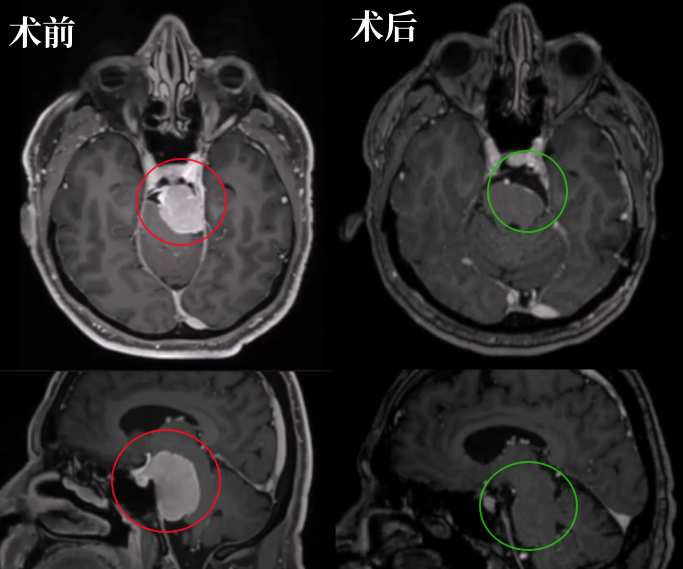

术前术后影像对比:肿瘤得到完全切除

术后情况:角膜炎在10天内消退,国际卫生组织II级脑膜瘤(已确诊),V3感觉减退在2个月后得到好转。

术后CT扫描未显示任何术后并发症。术后MRI显示脑膜瘤几乎完全切除,海绵窦后部有少量残留。

2、术后恢复情况